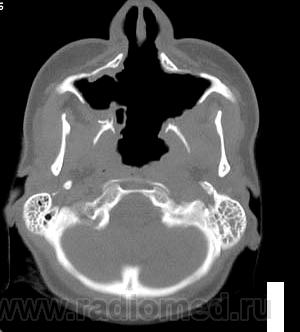

Кажется, это уже было - гранулематоз Вегенера, если не ошибаюсь.

Гранулематоз Вегенера

Деструктивный процесс в полости носа и в пазухах может представлять собой гранулематоз Вегенера. Требуется тщательное собрание анамнеза, учет клинической картины, и разумеется, биопсия.